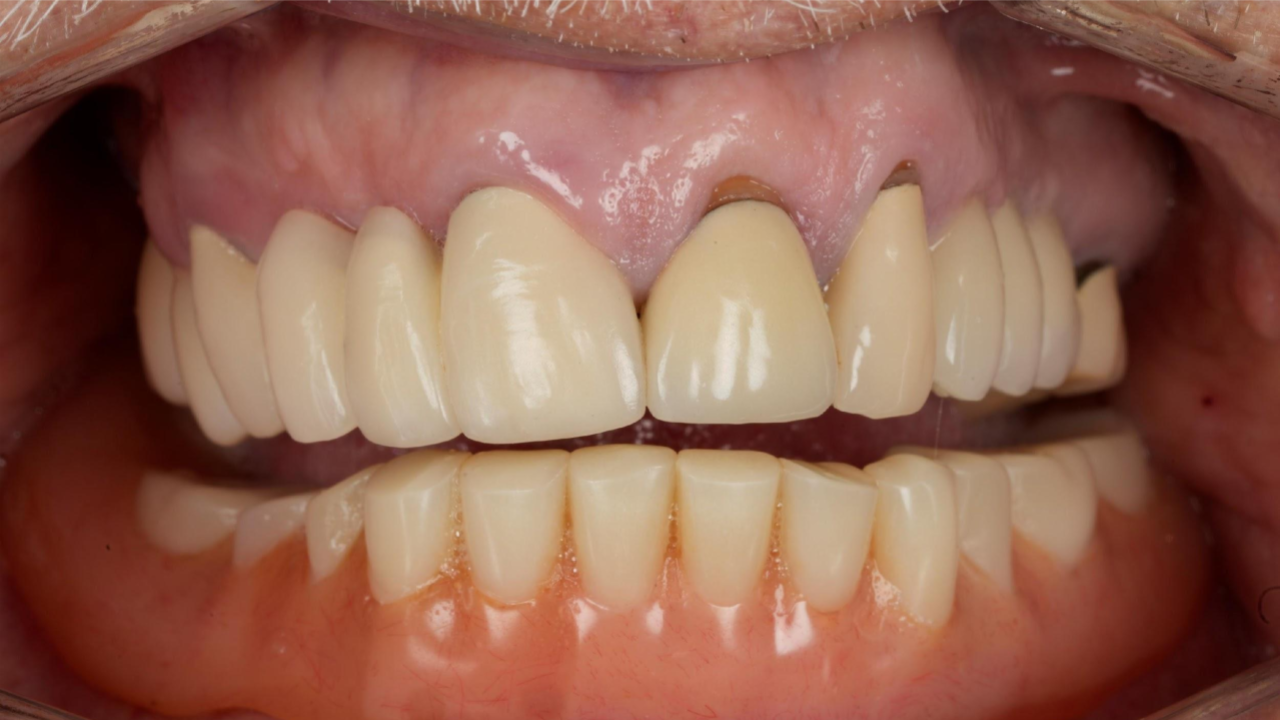

Preoperative radiograph Patient pre-op, retracted

The patient presented with a history of dental implants in the maxillary and mandibular arches. The remaining maxillary dentition exhibited failure, chronic infection, and inflammation.